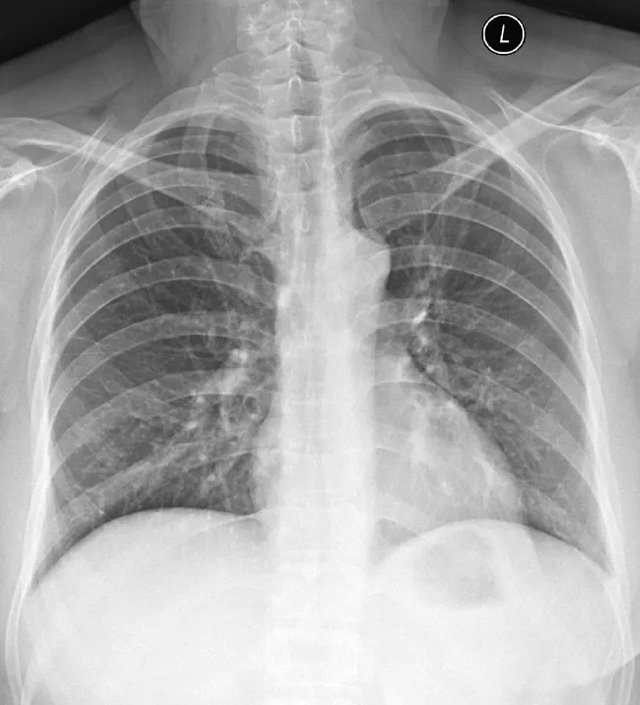

X線定位真空輔助旋切術(shù)是對(duì)臨床觸診和B超檢查均為陰性而X線片顯示的微小病變?cè)赬線立體定位引導(dǎo)下,將真空旋切刀置入乳腺可疑病灶區(qū)進(jìn)行旋切及組織病理學(xué)檢查的一種乳腺微創(chuàng)新技術(shù)。